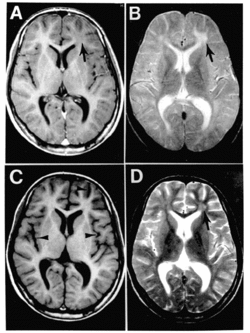

"SSPE is suspected in young patients with dementia and neuromuscular irritability. EEG, CT or MRI, CSF examination, and measles serologic testing are done. EEG shows periodic complexes with high-voltage diphasic waves occurring synchronously throughout the recording. CT or MRI may show cortical atrophy or white matter lesions. CSF examination usually reveals normal pressure, cell count, and total protein content; however, CSF globulin is almost always elevated, constituting up to 20 to 60% of CSF protein. Serum and CSF contain elevated levels of measles virus antibodies. Anti-measles IgG appears to increase as the disease progresses. If test results are inconclusive, brain biopsy may be needed."